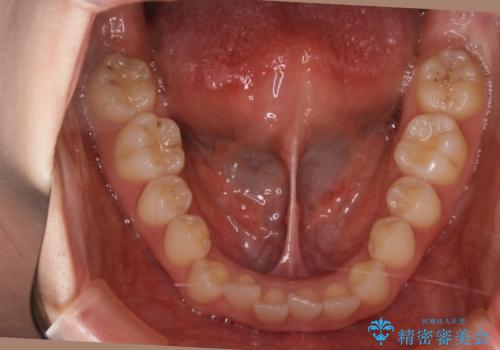

- 前から2番目の歯が捻じれていることが気になるとご相談にいらした方です。

インビザラインFULLで治療を行いました。

上の前から2番目の歯は、一般的に周囲の歯と比べて小さく、動きづらい歯であると言われています。前歯にゴムかけを行うことで理想的な位置まで歯を動かしてくることが出来ました。